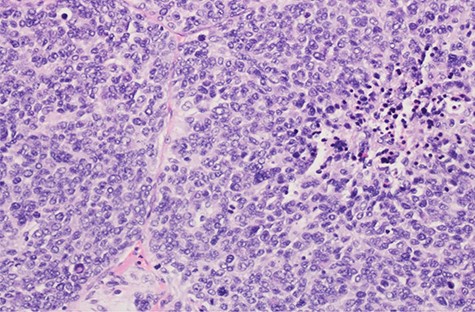

Pathologic evaluation demonstrated an 18 cm, 2 kg tumor emanating from the submucosa of the esophagus (Fig. 4). Remarkably, the mucosa remained intact. Periesophageal, gastric, hilar and mediastinal lymph nodes were negative. Margins were confirmed negative. There were 42 mitoses per HPF with 30% necrosis and histologic grade 3. Tumor markers showed positive for CD34, vimentin, BCL-2 and beta-catenin (membranous pattern); weakly positive for caldesmon and negative for CD31, DOG1, CD117, S100, smooth muscle actin, desmin and pancytokeratin. Foundation One testing revealed microsatellite status stable and tumor mutational burden low. Genomic findings revealed STAT6-NAB2-STAT6 fusion and TP53-Y205C (Fig. 5).